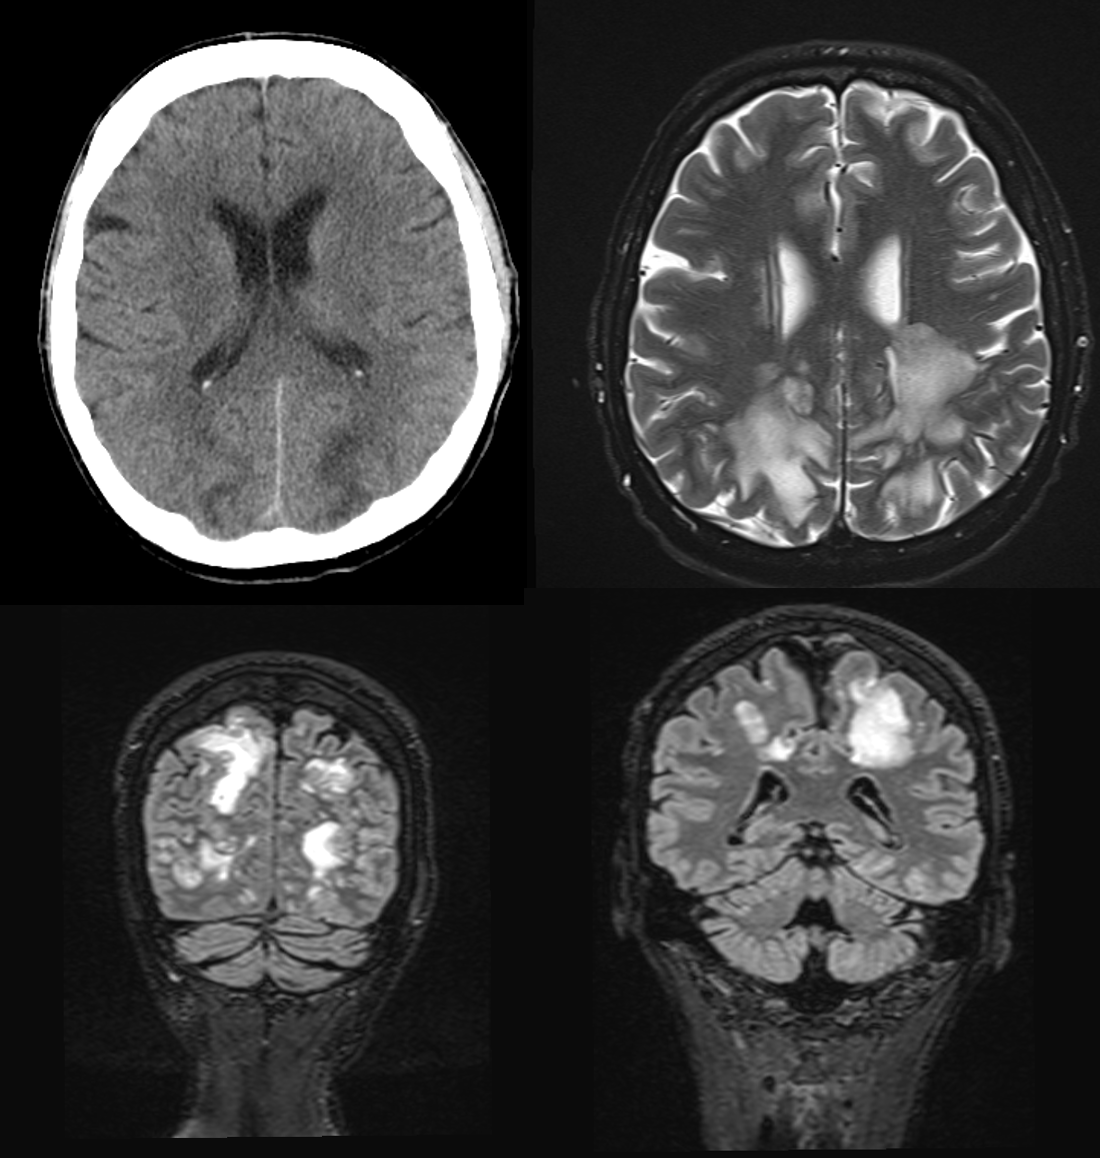

A computerised head tomography scan was performed to rule out an intracranial haemorrhage. Due to pathological findings, magnetic resonance imaging was subsequently performed.

MRI findings

The axial T2 as well as the coronal T2-FLAIR sequences show pronounced flat T2w-hyperintense areas in the parieto-occipital semioval center on both sides. The cortex was not affected. Furthermore, there was no evidence of intracranial haemorrhage. Image was compatible with vasogenic oedema in posterior reversible encephalopathy syndrome (PRES).